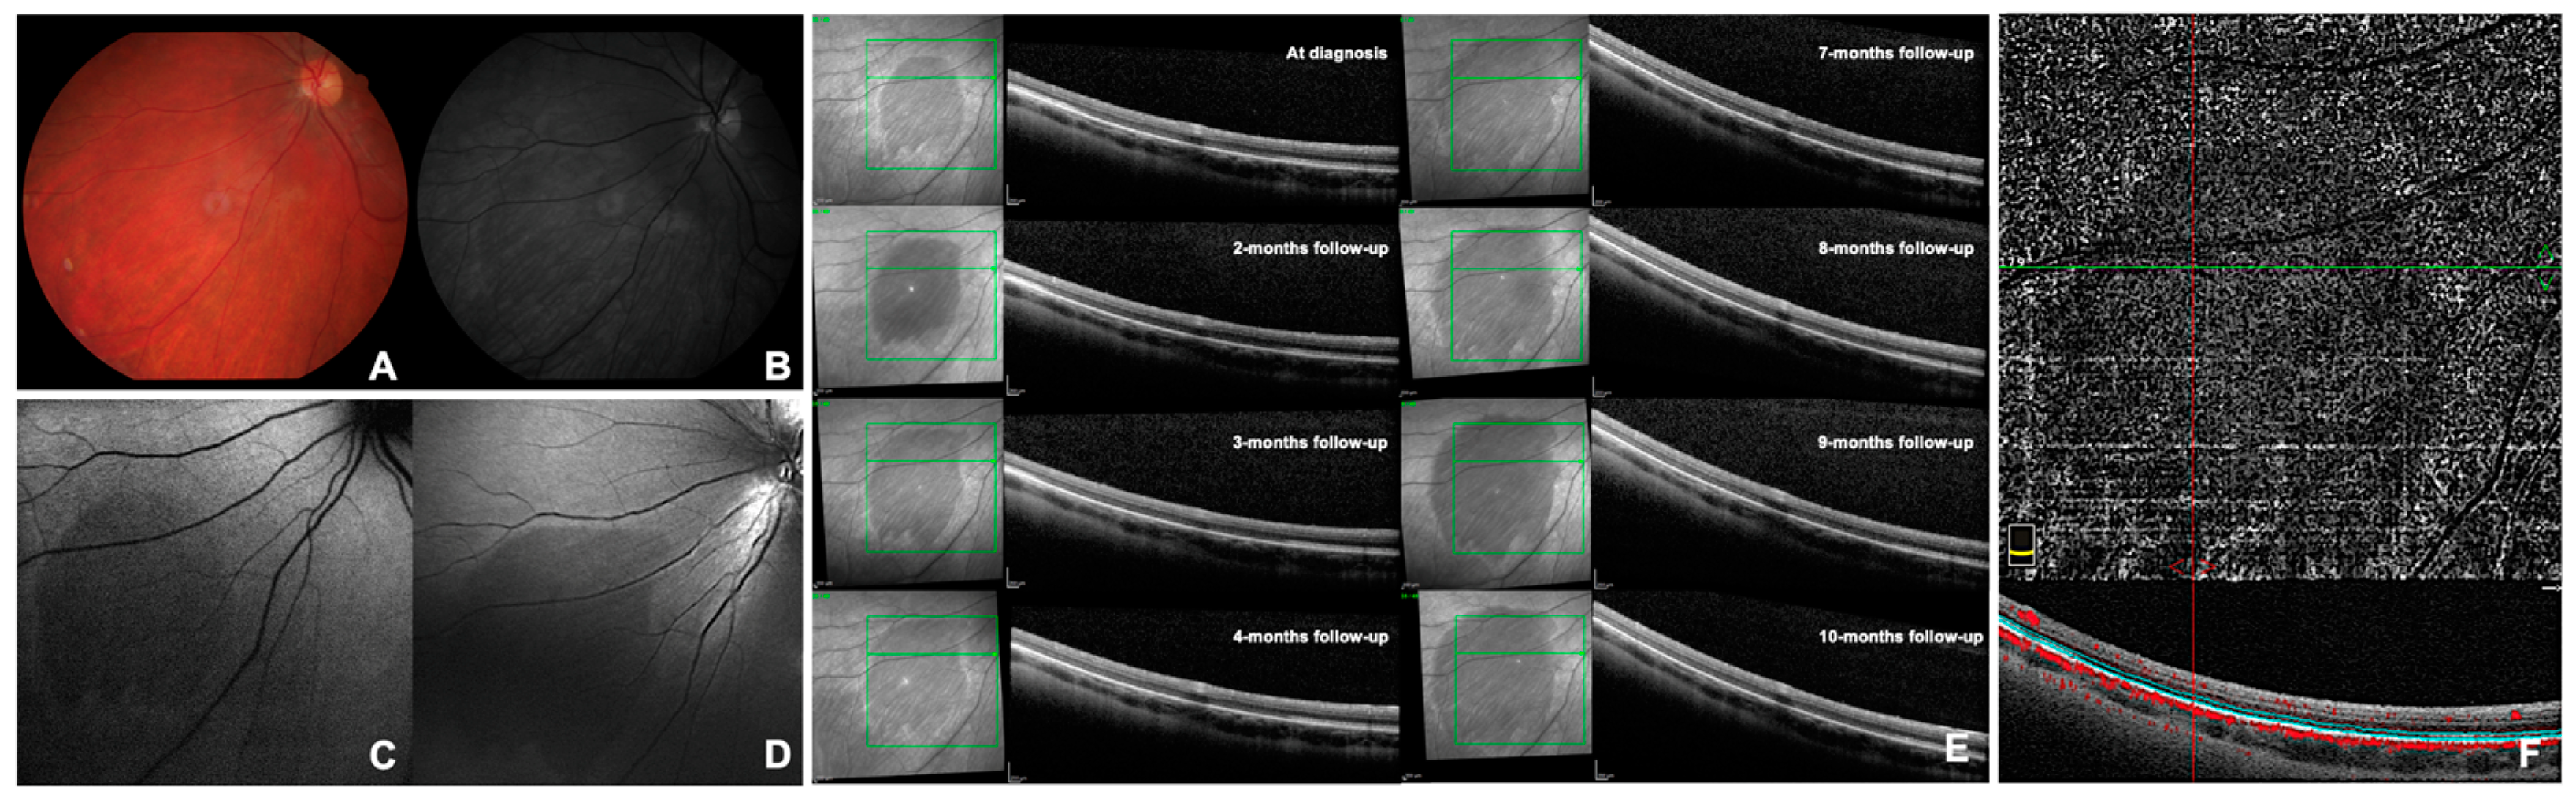

CASE 5. A 30-year-old Caucasian male presented to our Retina Center for a follow-up examination of an extrafoveal inactive fibrotic inflammatory macular neovascularization in the RE, previously treated by five aflibercept intravitreal injections. The patient was diagnosed with primary sclerosing cholangitis and supplemented with ursodeoxycholic acid. The patient was asymptomatic; his BCVA was 0.0 logMAR (20/20) in both eyes (spherical equivalent: −0.50 diopters in the RE and −1.00 diopters in the LE). The anterior segment of both eyes was within normal limits, and no signs of ocular inflammation were found. Fundus examination showed no changes in the RE but a crescent-shaped DWP area in the temporal mid-periphery of the LE adjacent to an area of white without pressure was detected. The lesion, measuring approximately 4 papillary diameters, had a well-defined inferior margin, while the superior margin was not (Figure 3A). DWP was slightly hypo-fluorescent on BAF while well-defined through BR and NIR retinography. The FA revealed a delay in perfusion of the vessels feeding the affected area, and the DWP lesion showed a faint mask hypo-fluorescence all along the exam duration (Figure 3B). On ICGA, the spot remained not visible except for the temporal hypo-fluorescent margins in the late-intermediate phase (Figure 3C). OCT examination showed that the hypo-reflective area corresponded to an attenuation of the reflectivity of the EZ band (Figure 3D). The OCT-A was of poor quality due to the lesion location but demonstrated findings like Cases 2 and 3. The 30-2 SITA-SAP showed paracentral relative scotomas in the RE attributable to previous macular neovascularization, while the LE was within normal limits. The 60-4 SAP was unremarkable in both eyes and the standard ERG was within normal limits in both eyes. The DWP lesion demonstrated a progressive reduction in size over time, as demonstrated by follow-up OCT scans performed at 2, 4 and 8 months. The size reduction of the lesion at NIR was correlated to the gradual restoration of EZ band reflectivity on OCT (Figure 3D). After 20 months, the DWP lesion appeared significantly reduced in extension in the lower part, but the superior and temporal margins had widened (Figure 3D). The patient reported having a flu-like episode 2 weeks earlier with no ocular symptoms.

Figure 3. Selected images of dark without pressure from Case 5 (see text). Panel (A) shows color retinography at the time of the diagnosis. Panel (B) shows the early and mid-phases of fluorescein angiography at the time of diagnosis. Panel (C) shows the indocyanine green angiography phases at the time of the diagnosis. Panel (D) shows the infrared optical coherence tomography at the time of the diagnosis and the subsequent follow-ups.